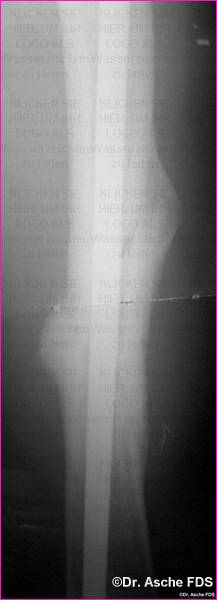

Osteosynthese mit PFN

Die Osteosynthese war primär nicht belastungsstabil

Nach Belastungsbeginn kommt es zur Varisierung durch

den dünnenNagel

Bereits primär lag ein Drehfehler von 13° vor.

Der Patient konnte nach 6 Monaten nicht schmerzfrei laufen.